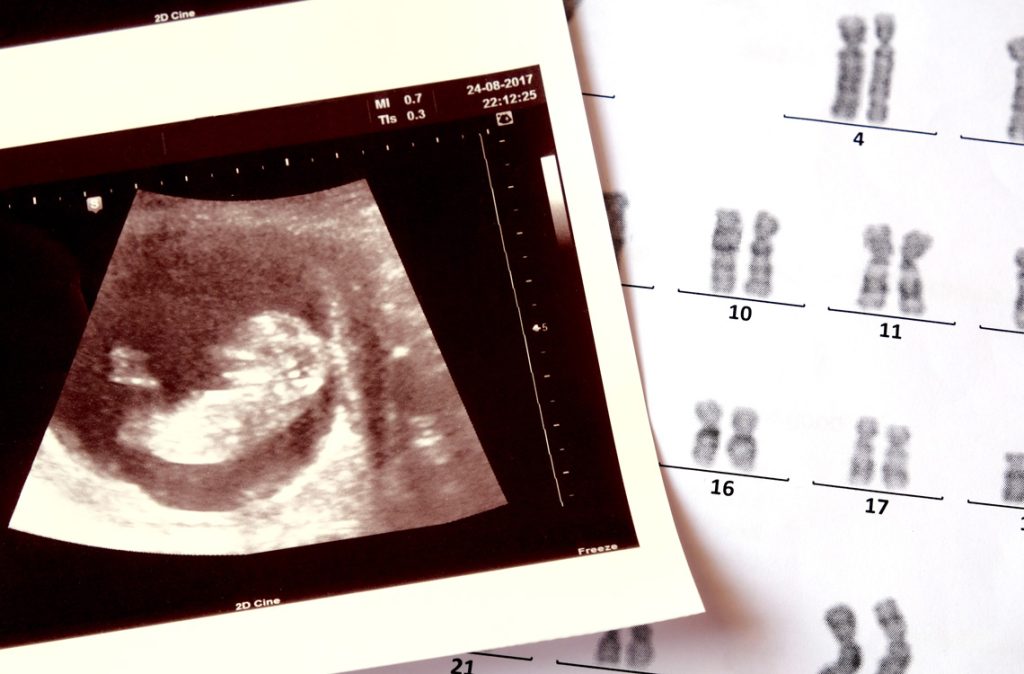

Down syndrome, also called trisomy 21, is a genetic condition. It happens when a baby has an extra copy of chromosome 21.

The condition is usually picked up through prenatal screening or diagnostic tests.

You may have had a combined screening in early pregnancy or a non-invasive prenatal test (NIPT).

If the results were high risk, your healthcare provider may have recommended a diagnostic test like amniocentesis.

These tests are accurate and can confirm the condition before birth.